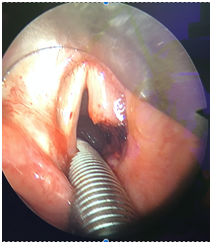

In our study, all patients had a tracheostomy tube insitu before CO2 laser cordectomy. Yet this procedure can be safely done without a tracheostomy and may avoid doing one. In fact, endoscopic management of BVCP whether CO2 laser cordectomy or arytenoidectomy has proven to be more cost effective on the long term compared to tracheostomy.9 Endoscopic management of BVCP without tracheostomy can be performed with suspension microlaryngoscopy with spontaneous ventilation, apneic technique, or using laser safe metallic endotracheal tubes (Figure1). Laser cordectomies can be performed simultaneously on both vocal cords. Olthoff and Steiner have showed that this bilateral technique combines excellent airway improvement and satisfactory voice preservation.10

Figure 1 Microlaryngoscopic view showing end result after right CO2 laser cordectomy. Note the presence of laser safe tube used during the procedure.